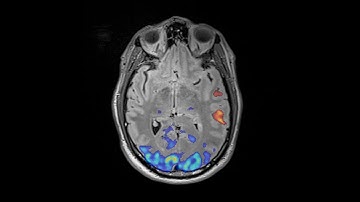

Surgeons create personalized brain maps to guide safer surgeries